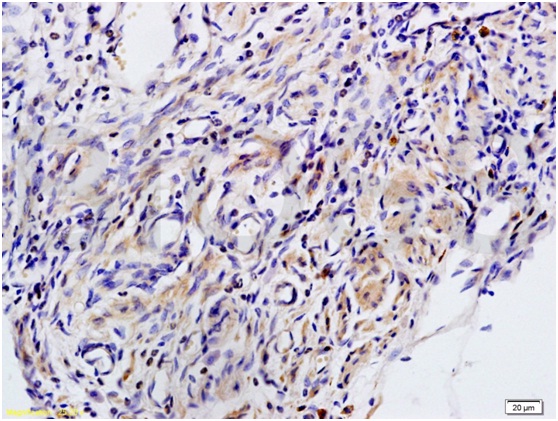

Antigen retrieval: citrate buffer ( 0.01M, pH 6.0 ), Boiling bathing for 15min; Block endogenous peroxidase by 3% Hydrogen peroxide for 30min; Blocking buffer (normal goat serum,C-0005) at 37℃ for 20 min;

Incubation: Anti-MIP2/GRO Beta/CXCL2 Polyclonal Antibody, Unconjugated(bs-1162R) 1:200, overnight at 4℃, followed by conjugation to the secondary antibody(SP-0023) and DAB(C-0010) staining